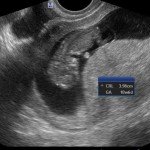

E’ un esame ecografico che consiste nella misurazione, tra la 11esima e la 13esima settimana, di uno spazio situato nella regione posteriore del collo fetale. In tale sede è presente una sottile falda di liquido che è presente nella regione nucale di tutti i feti e che appare all’esame ecografico come una sottile zona liquida detta translucenza. Quando tale falda fluida è aumentata (aumento di spessore della translucenza nucale) può esservi un maggior rischio di patologie cromosomiche fetali o altre patologie, ad esempio cardiopatie malformative. Oltre alla translucenza nucale, si esegua ovviamente una accurata valutazione della morfologia fetale, per quanto possibile in relazione all’epoca di gravidanza.

L’associazione del Bi-Test con la misurazione ecografica della Translucenza nucale ha una sensibilità per la Sindrome di Down del 90% (è cioè in grado di individuare 90 feti su 100 affetti da sindrome di Down).